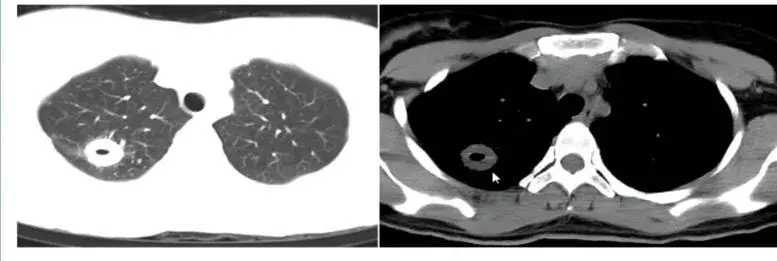

8. 机化性肺炎

机化性肺炎临床多持续存在,影像学表现为有分叶,并出现胸膜凹陷的情况。值得注意的是,机化性肺炎和真菌感染形成的肉芽肿在进行PEC-CT时摄取值同样增高,容易造成误诊。机化性肺炎通常与胸膜有牵连,胸膜出现收缩,但并非牵拉,为局限性的胸膜凹陷。

厚壁空洞,增强后厚薄不一,小叶间隔,容易误诊为肺癌。

1599963394958_fb02f9c2j00qgk3gi000yd200mu009fg00g0006l.jpg

图11 出现厚壁空洞的机化性肺炎表现